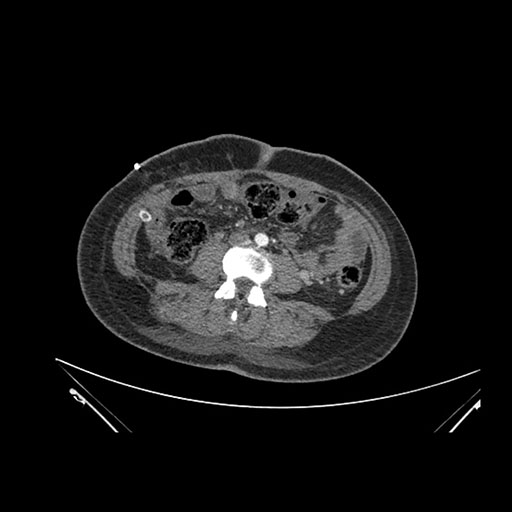

Imaging Analysis

Look through the patient's CT scan to identify any areas of concern for the necessary procedure.

Coronal Arterial

Based on initial findings, which issue(s) would you be most concerned about?